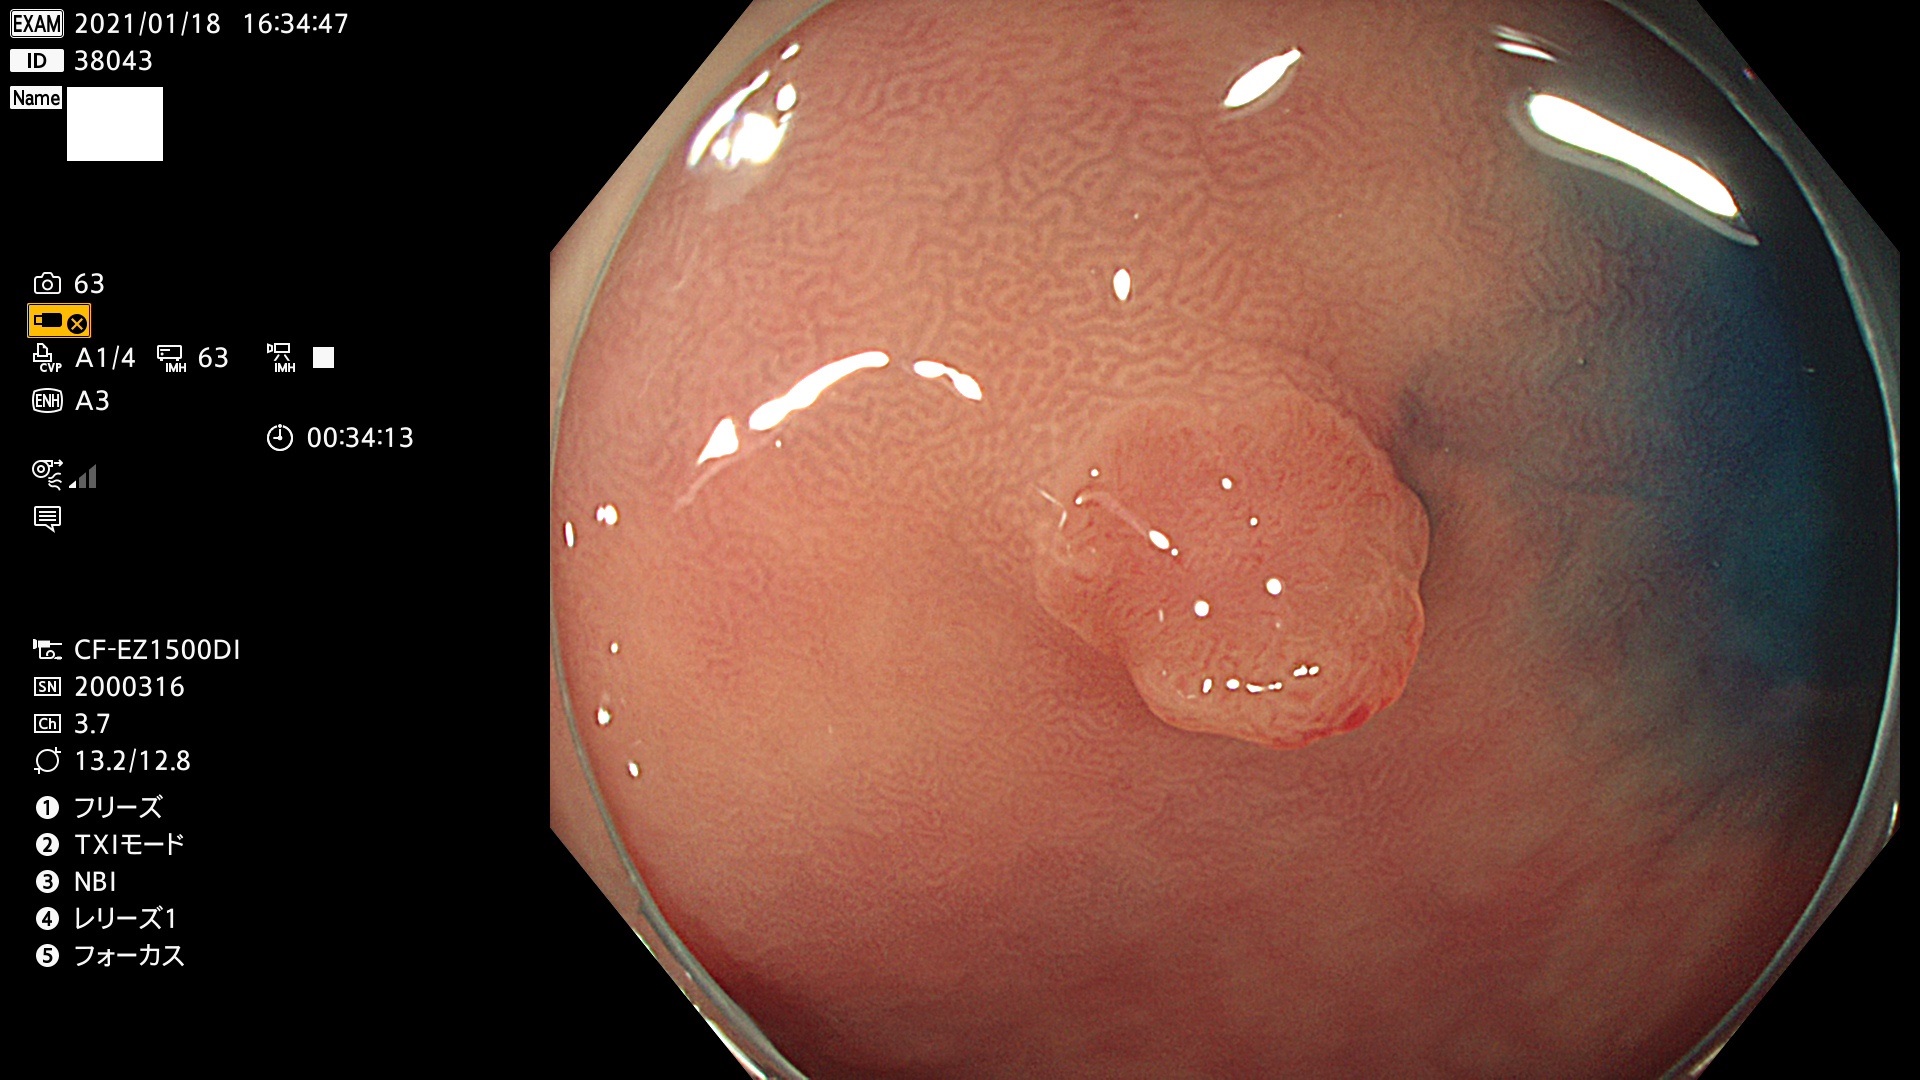

38001 38002 38003 38004 38006(SSAPのみ) 38007 38008 38009 38010 38012 38013 38014 38016 38018 38020 38021 38025 38026 38029 38032 38033 38034 38035 38036 38037(SSAPのみ) 38039 38043 38044 38048 38049 38050 38052 38055 38056 38057 38058 38059 38064(SSAPのみ) 38065 38068 38069 38070 38071 38072 38074 38075 38076 38078 38079 38080 38082 38083 38084 38085(SSAPのみ) 38086 38087 38088 38089 38090 38091 38092 38093 38094 38097 38098 38099

発見困難で危険性の高い平坦型病変(上記100名より抽出)